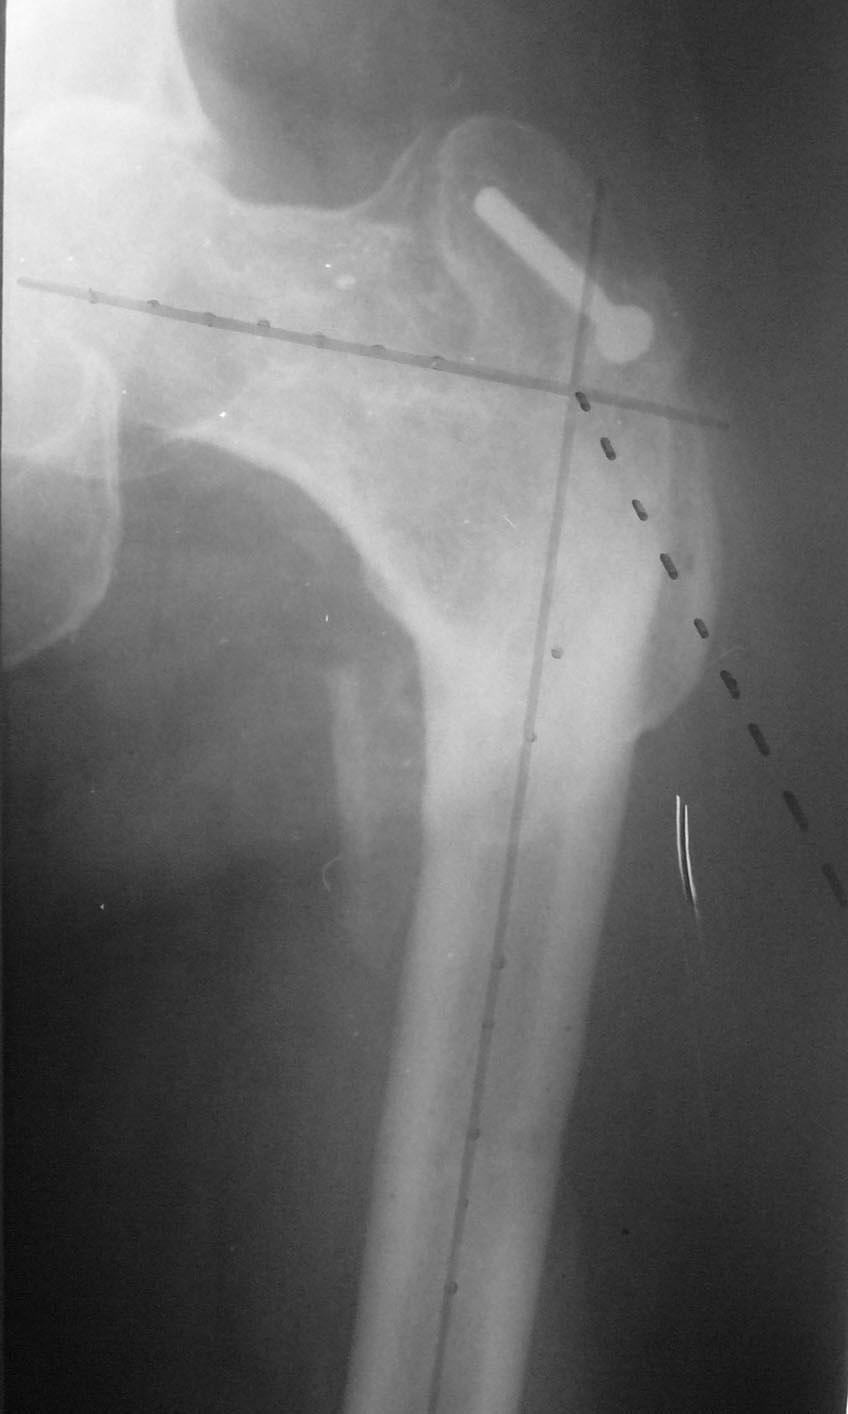

Приложенный пример - не строго по рассматриваемому случаю. Но, может быть, кому-нибудь пригодится.

Здесь вариант преоперационного планирования, где дорисованные верлужная впадина и кортикальные слои костей лучше подчеркивают "скиаграмму"..